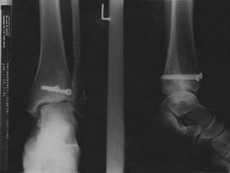

Für die nächsten sechs Wochen sind Rollstuhl und Krücken angesagt...